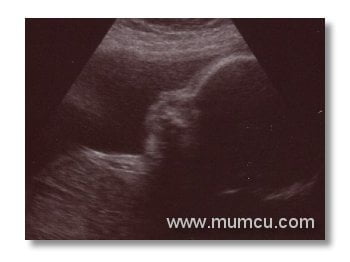

6 haftalık ikiz gebelik

Vajinal ultrasonografi